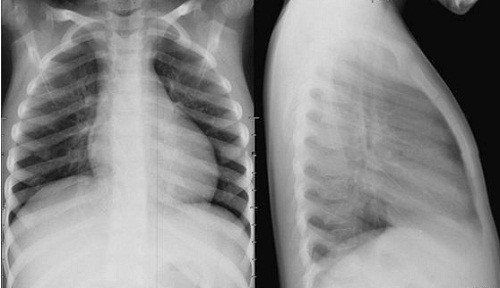

Chụp x quang tim phổi thẳng dựa trên nguyên lý dùng quang tuyến X để đánh giá hình ảnh của các cơ quan tổ chức trong cơ thể thông qua mức độ hấp thụ nhiều hay ít tia X của từng cơ quan, tổ chức khác nhau, để tạo ra hình ảnh với những vùng sáng đậm nhạt khác nhau trên phim.

- Chụp x quang tim, phổi thẳng sẽ thâm nhập vào các cấu trúc cơ thể và mô theo những cách khác nhau. Xương rất dày đặc và các khối của bức xạ, vì vậy hình ảnh của xương trên phim xuất hiện màu trắng. Trái tim cũng ngăn chặn một số bức xạ và do đó xuất hiện như một khu vực nhẹ hơn trên phim. Phổi chứa đầy không khí, vì vậy khối nhỏ của bức xạ, tạo ra một hình ảnh đen tối.